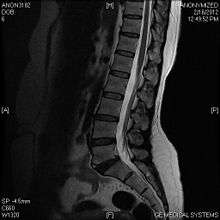

Limbus vertebra

A limbus vertebra also see vertebral epophysis is a bone trauma in the vertebral body bearing a radiographic similarity to a vertebral fracture. The anterior-superior corner of a single vertebra is the common site for this defect although it can also be seen at the inferior corner as well as the posterior or anterior margin. Anatomically, it is assumed to be an intra-vertebral body herniation of the disc material occurring during adolescent growt spurt when the ring apophysis has not yet fused. It was first described by Schmorl in 1927 and later in detail by Leif Sward and Adad baranto.

Viewed in a lateral radiograph, it appears as a triangular shaped bone fragment, not unlike an anterior lip fracture, but with softer edges.

Limbus vertebra is not always symptomatic, but severe cases may lead to more serious pathological conditions and chronic pain. In rare instances, a posterior limbus vertebra has been described causing radiculopathy due to nerve root compression.